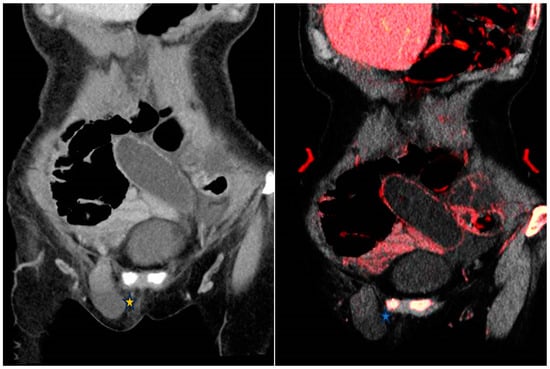

5.2.1. Urolithiasis

5.2.2. Inflammation, Neoplasm and Hemorrhage